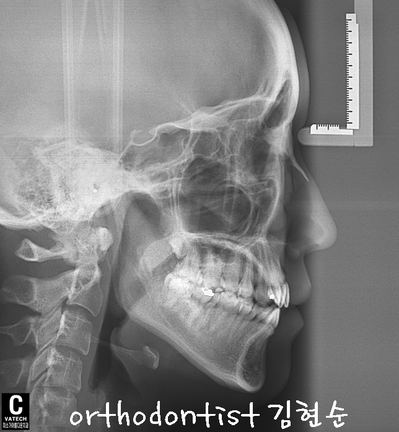

세라믹 치과 김현순 대표 원장님 -

개방 교합 -

교정 문의 환자 : 김 0 0

나이 : 24 세 F

교정 사유 : 앞니 / 치열 / 교합